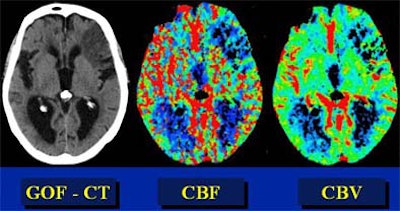

In recent years, researchers have performed CT studies that demonstrate the same information. Initial-phase CT will show ischemic penumbra as a region of normal or increased cerebral blood volume (> 2.5 ml per 100 g of brain tissue) in the region, combined with a decrease in CBF of more than 34%, he said. Once the tissue dies, CBV will also decrease.

"So decreased CBV is dead brain, whereas normal or increased CBV in the setting of decreased CBF is penumbra," he explained. Parametric color maps based on CBV, CBF, and mean transit time (MTT) can be used to illustrate the penumbra.

| In an elderly male patient, parametric color maps from perfusion CT show dramatic ischemia in the left hemisphere. In the area of the box, cerebral blood flow (CBF) is decreased (> 34%), cerebral blood volume (CBV) is increased (> 2.5 mL per 100 g of brain tissue), explaining the long mean transit time (MTT), and indicating potentially salvageable brain tissue. However, in the region below the box, substantial matching of blue areas (CBF and CBV) indicates infarcted tissue that is not salvageable. Images courtesy of Dr. Jay Cinnamon. |